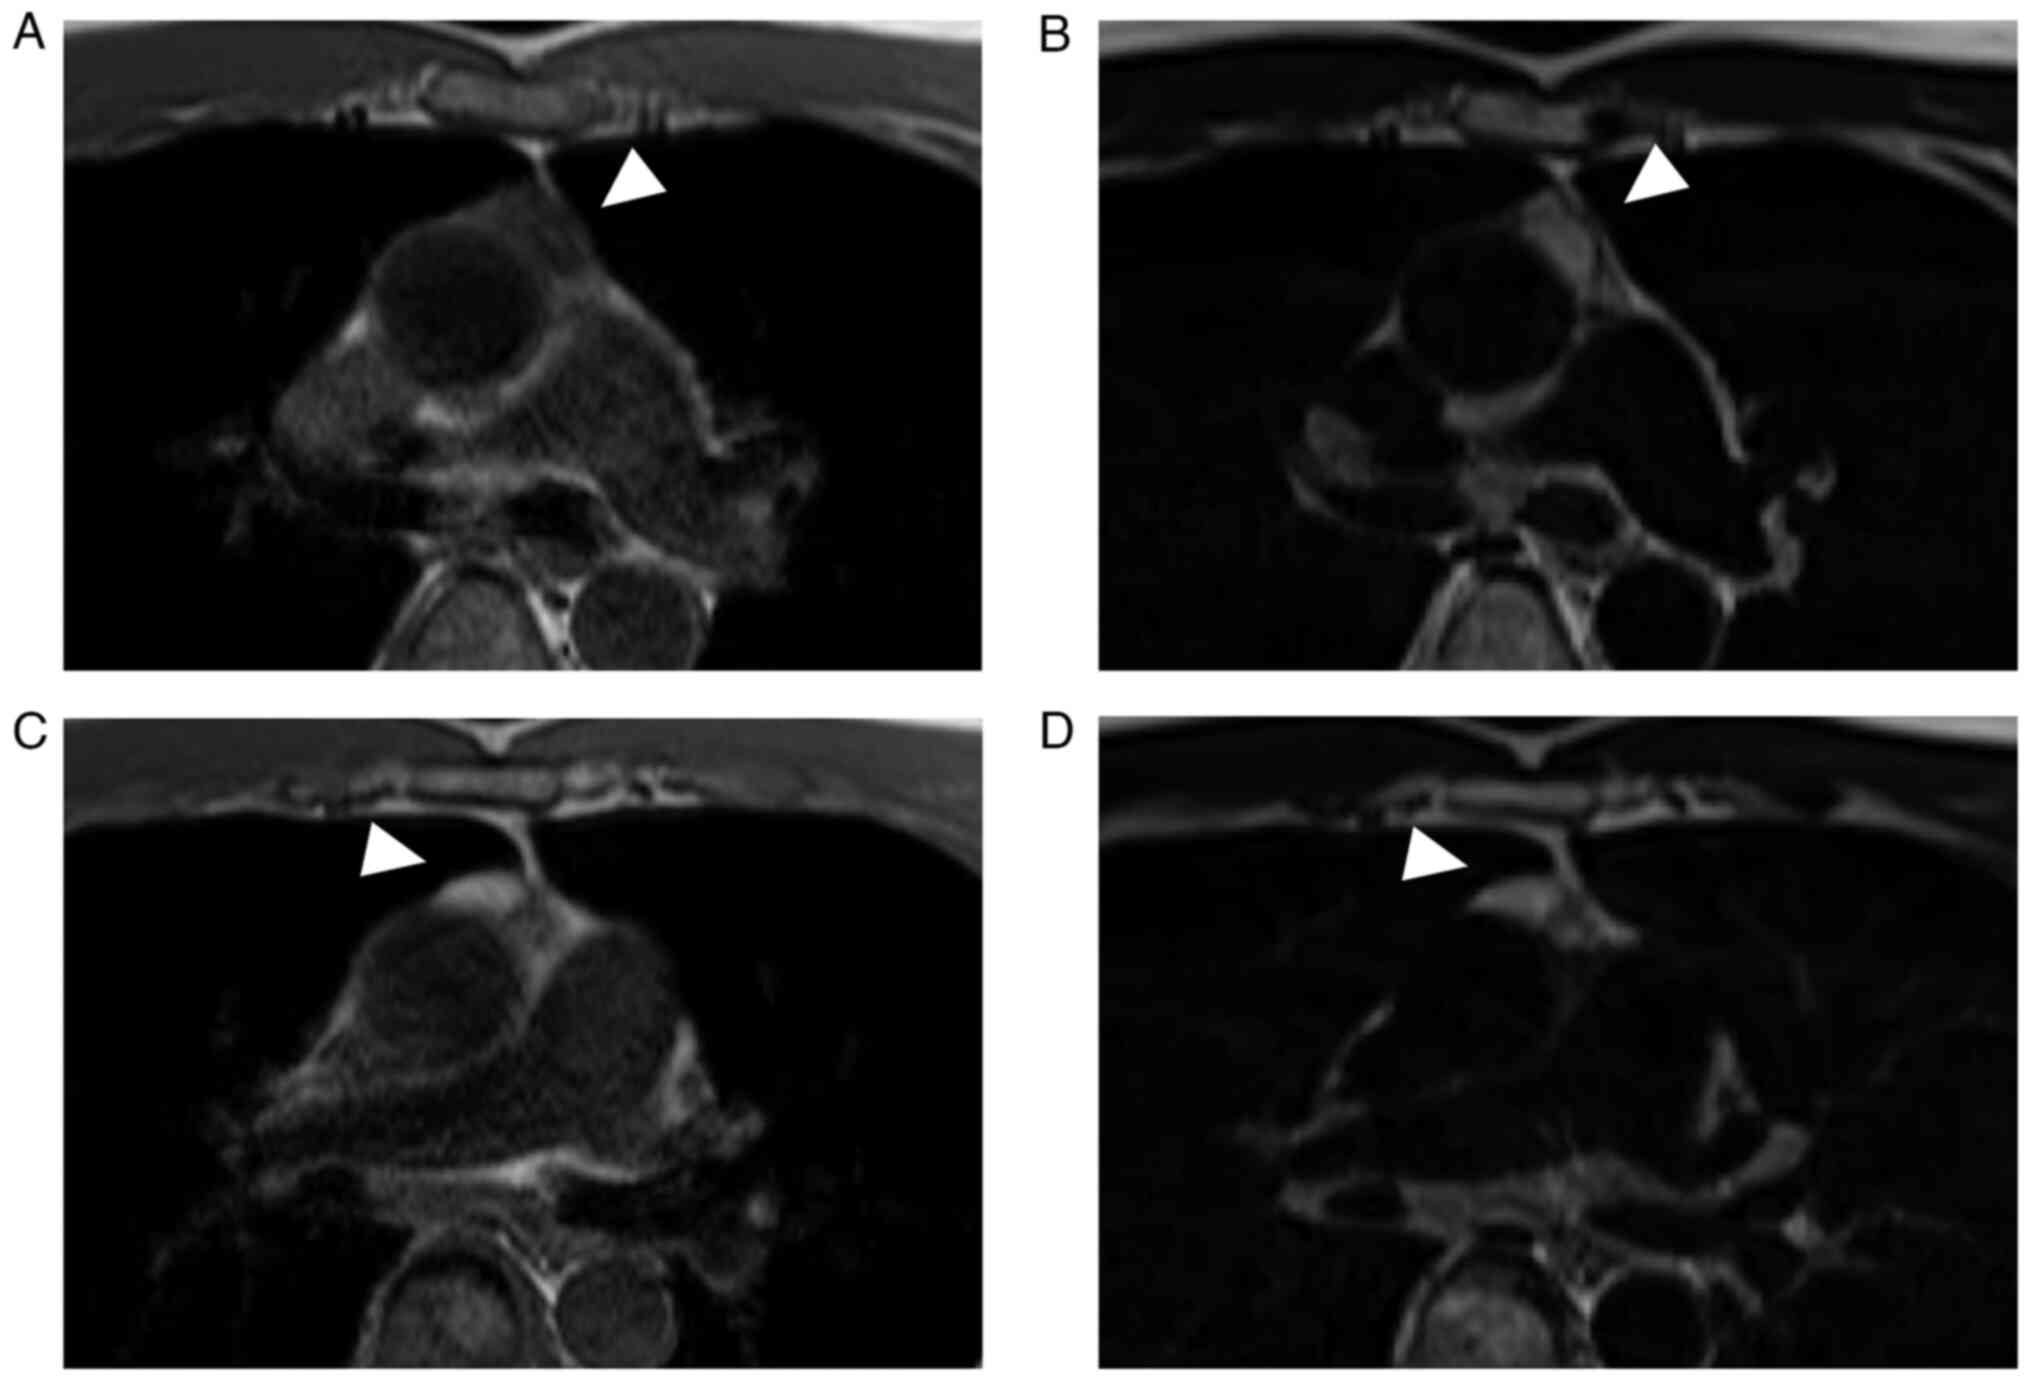

A 52-year-old man with a 20-year history of HIV infection who was undergoing antiretroviral therapy was admitted to our hospital with a COVID-19 pneumonia. On CT scan performed on day 9 of COVID-19, an anterior mediastinal tumor was incidentally detected (Fig. 1). There was no history of smoking, and the clinical history included type-1 diabetes mellitus (Islet Antigen-2 antibody positive), hypertension, renal failure, and syphilis. The patient was asymptomatic with no notable findings on physical examination. Blood examination showed renal dysfunction (urea nitrogen, 25.7 mg/dl; creatinine, 2.41 mg/dl) and hyperglycemia (fasting blood sugar, 112 mg/dl; hemoglobin A1c, 8.3%; glycoalbumin, 21.0%). Rapid plasma reagin, Treponema pallidum antibody, HIV antigen, and HIV antibody tests were positive. Anti-acetylcholine receptor antibody test was negative, ruling out the possibility of myasthenia gravis. There was no significant elevation in tumor markers, including human chorionic gonadotropin β, alpha-fetoprotein, squamous cell carcinoma antigen, cytokeratin 19 fragments, and carcinoembryonic antigen. Regarding HIV control, the cluster of differentiation 4 count was decreased (576/µl), and the HIV RNA load was less than 20 copies/ml. Magnetic resonance imaging revealed a 28-mm bilocular cyst. One of the two chambers showed low intensity on T1-weighted images and high intensity on T2-weighted images, whereas the other chamber showed high intensity on both T1-weighted and T2-weighted images. No infiltration of the capsule or adjacent organs was observed (Fig. 2). As malignancy could not be excluded, robot-assisted thoracoscopic resection of the anterior mediastinal tumor was performed.

Magnetic resonance images showing a 28-mm bilocular cyst (white arrow). One of the two chambers shows (A) low intensity on T1-weighted images and (B) high intensity on T2-weighted images, whereas the other chamber shows high intensity on both (C) T1-weighted and (D) T2-weighted images.